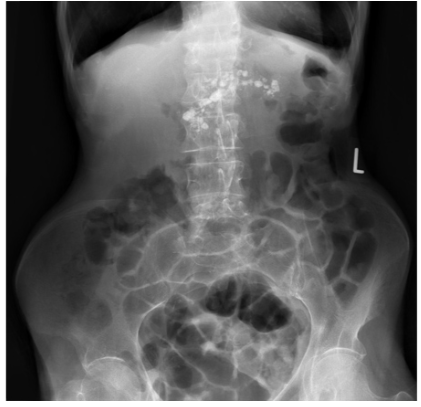

Patient with severe abdominal pain. What does the image show?

Ascites

Lead pipe colon

Normal gas pattern

Rigler’s/ double wall sign

Thumbprinting

Inflammation of the bowel wall leads to thickening of the haustral folds. This results in the radiological sign of thumbprinting, a characteristic finding in patients with active ulcerative colitis.